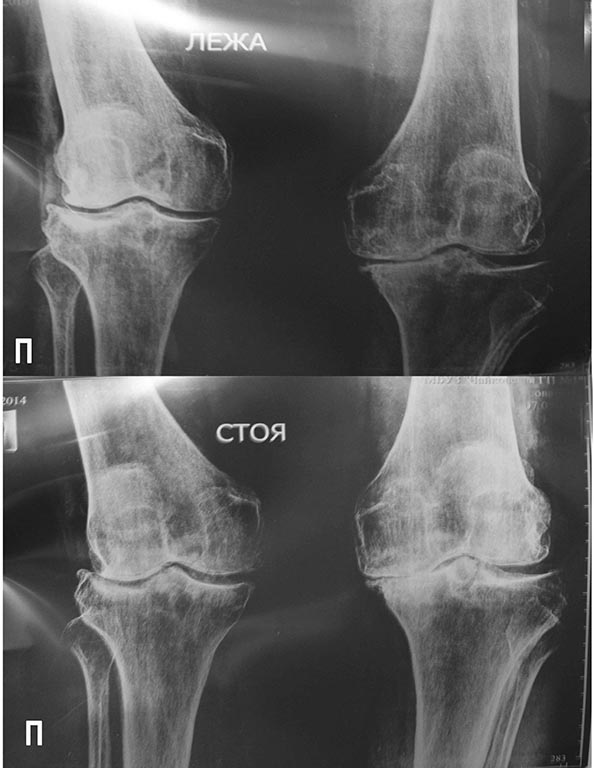

Обратилась женщина 1945 года рождения по поводу вальгусной деформации правой голени.

Со слов, деформация образовалась в течение года. Травму исключает.

А что у больной с минеральной плотностью кости? судя по снимкам имеет место быть выраженный остеопороз. по-моему нужно протезировать.

Для остеотомии похоже поздновато (слишком большие разрушения в суставе). Если нацелились непременно на остеотомию - нужен осевой снимок.

Еще имеет смысл дообследовать, не стоит забывать про charcot joint и SPONK, хотя картина нетипичная, но все же, учитывая быстрый прогресс заболевания.

Перед тем как что то делать с коленным суставом, необходимо разобраться с правым тазобедренным, т.к. похоже вальгус коленного связан с коксом справа и приводящей контрактурой в т\б суставе. Первичное протезирование коленного сустава в этой ситуации только усугубит состояние пациента. Сначала т\б сустав. С уважением В.М. Николаев.